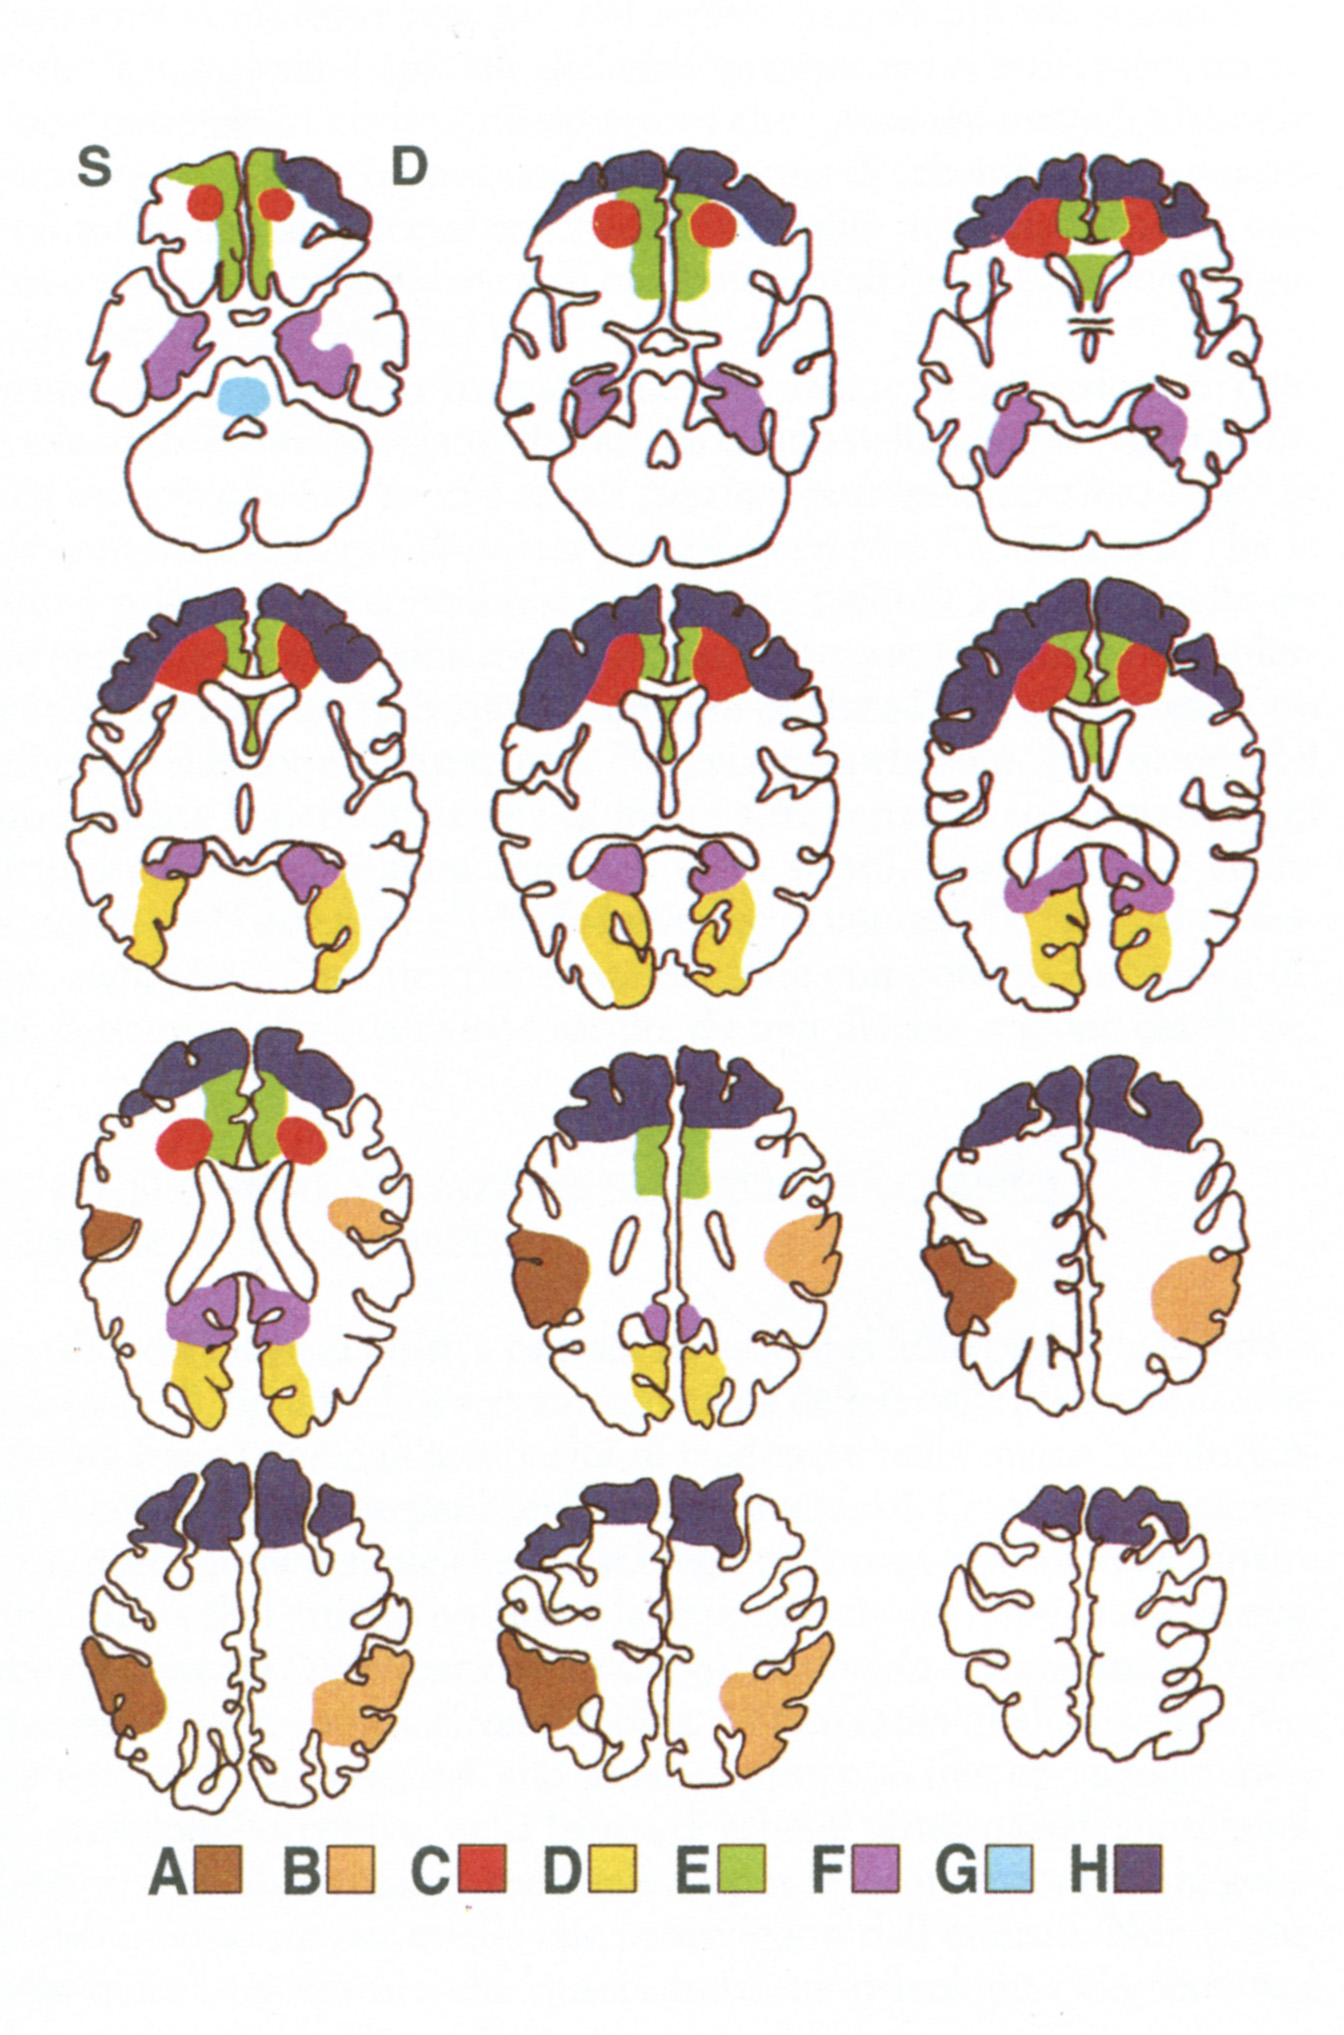

Di ciascuno di questi elementi fondamentali dei movimenti volontari sono responsabili principali varie strutture cerebrali, rispettivamente: le aree sensoriali della corteccia postcentrale, le aree parieto-occipitali, i gangli della base e le aree premotorie, i lobi frontali. A seconda di quali di queste strutture vengono lese, si hanno disturbi differenti del movimento volontario e cioè forme diverse di aprassia, note rispettivamente come aprassia cinestetica, aprassia spaziale, aprassia cinetica e aprassia dell'intenzionalità (tav. 6).